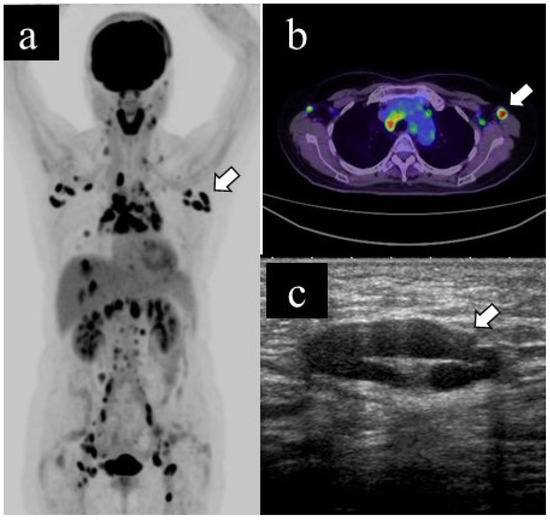

Figure 2 and Figure 3 show representative cases of benign and malignant lymphadenopathy, respectively.

The patient, in her 70s, underwent a PET scan for follow-up after renal carcinoma surgery, which revealed an unexpected abnormal uptake in the left axillary lymph node (a. b). US examination revealed lymphadenopathy (long diameter: 21.8 mm, short diameter: 13.1 mm, cortical thickness: 13.1 mm, loss of fatty hilum) (c); subsequently, she underwent US-guided FNA. The cytological classification was class V. The patient underwent axillary lymph node dissection and was finally diagnosed with axillary lymph node metastasis of renal carcinoma.

Figure 3. Representative case of malignant lymphadenopathy. (a) Maximum-intensity projection (MIP), (b) transaxial 18F-FDG PET/CT image and (c) US image of malignant lymphadenopathy.